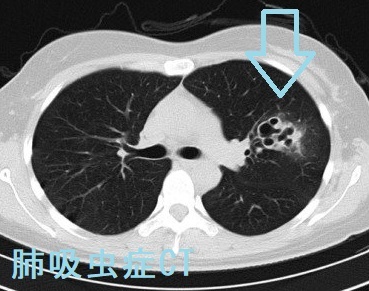

肺吸虫症

肺吸虫症は食品由来の寄生虫病で、ウエステルマン肺吸虫症と宮崎肺吸虫がほとんど。肺吸虫の第2中間宿主、淡水産のカニ(サワガニ、モクズガニ、上海ガニ、アメリカザリガニ)の生食もしくは十分火が取っていない半生食、カニを食べるイノシシの生肉を食べて感染。韓国では、淡水産カニを生で食べるらしいが、日本で刺身にするのは海にいるズワイガニだけのはず。

肺吸虫の幼虫は小腸壁から腹腔内→横隔膜→胸腔内(気胸、胸水、胸膜)→肺に移動(咳、痰、喀血)。

胸部CTでは

1. 気胸、胸水、胸膜肥厚など

2. 虫の移動による虫道が索状陰影(虫道)、周囲にすりガラス影を伴う結節、小葉間隔壁肥厚

3. 虫嚢が不整形の結節・浸潤影になり、甲状腺がんの肺転移、肺癌との鑑別要。空洞を伴うことも(J Korean Med Sci. 2012 Nov;27(11):1428-32.)

抗ウエステルマン肺吸虫抗体陽性。治療は吸虫駆除剤のプラジカンテル

肺吸虫症 CT